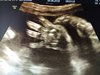

Wróciłam właśnie z USG prenatalnego, synek zdrowy waży prawidłowo 1499 g termin według USG 13.08 także też się zgadza. Jedyne co to cała ciążę siedział głową w dół a teraz obrócił się i jest miednicowe. Zobaczymy czy się jeszcze obróci a jak nie to albo rodzę miednicowe albo CC zależy co lekarz powie. Pomachał nam na USG ładnie rączka:) i ma dokładnie takie same wargi nosek jak córka.

Załączniki

• IMG_20180604_085629.jpg

IMG_20180604_085629.jpg

2,3 MB · Wyświetleń: 108

• IMG_20180604_085601.jpg

IMG_20180604_085601.jpg

1,5 MB · Wyświetleń: 101